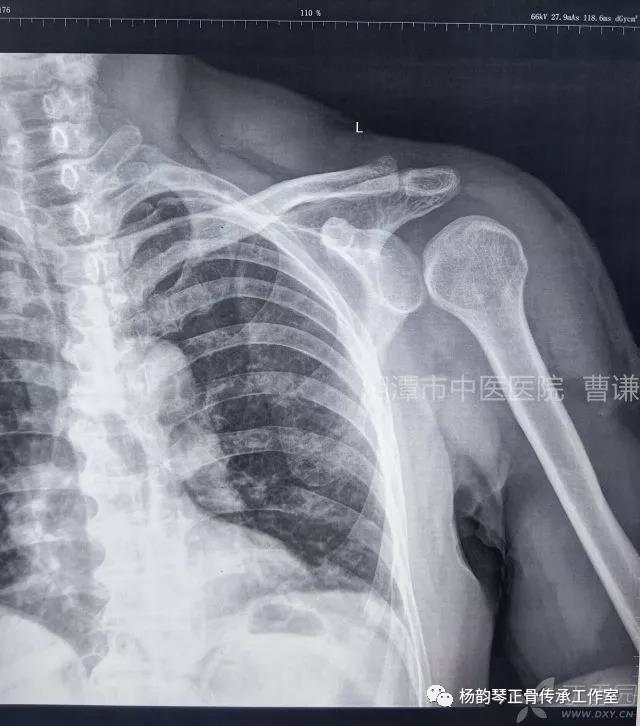

当地接诊医生应该说还是很负责的,同时拍了健侧片对比:

影像科报告,骨科医生光看报告行吗?